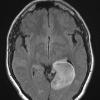

NEOPLASMS (GLIAL)

Astrocytoma, IDH-mutant, WHO Grade 2 (2)